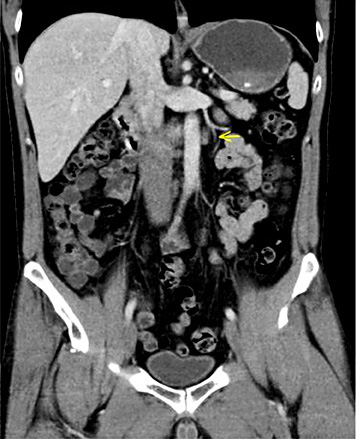

5th patient: this 23-year-old man underwent orchiectomy for marker-negative testicular seminoma at another institution. CT revealed intrathoracic nodules suspicious for mediastinal lymph node metastases. Accordingly, 4 cycles of BEP chemotherapy were administered. Restaging revealed unchanged mediastinal lymphadenopathy (Fig. 4). Then, the patient was referred to our institution for further management. Thorough pulmonological examination including transbronchial biopsy disclosed sarcoidosis-like lymphadenopathy, and thus metastatic disease was excluded. In view of these results, it must retrospectively be assumed that this patient had sarcoidosis synchronously with seminoma rather than having metastatic disease. Accordingly, the serum miR371a-3p level was RQ = 0.0 at the time of re-staging after chemotherapy. Unfortunately, no miR-levels were measured at the time of first presentation. Although speculative, one would assume that miR371a-3p levels had probably been low after orchiectomy for seminoma because the mediastinal lymphadenopathy had not changed ever since. By retrospective consideration, the normal marker level would have indicated the absence of metastases at the outset and accordingly, the patient could have been spared unwarranted chemotherapy and excessive diagnostic procedures apart from emotional distress from extended treatment.